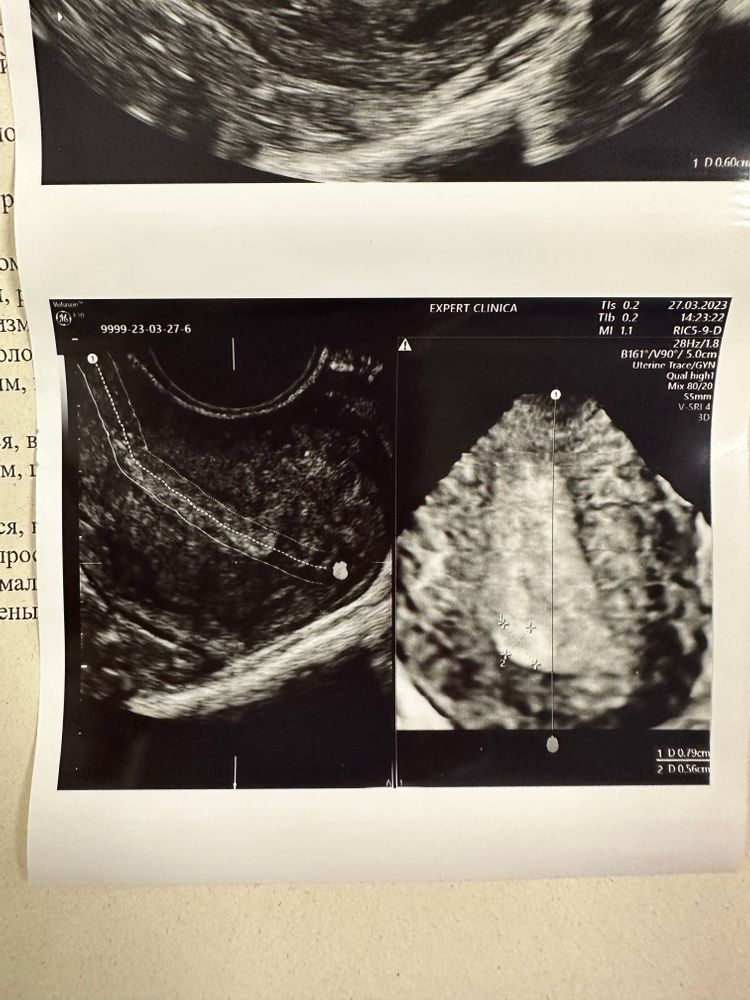

Но имеем опять в матке непонятное образование. Почему опять? Потому что в прошлый цикл во вторую фазу его другой узист тоже увидела, описала она его так: аваскулярное анэхогенное кистозное включение 5,8 на 3 мм. Сегодня у другой узистки это - включение 5,3 на 3,8 мм. Кровотока нет, но 100% уверенности в том, что это не полип, у нее тоже нет. Ставит под вопросом сгусток? / полип?